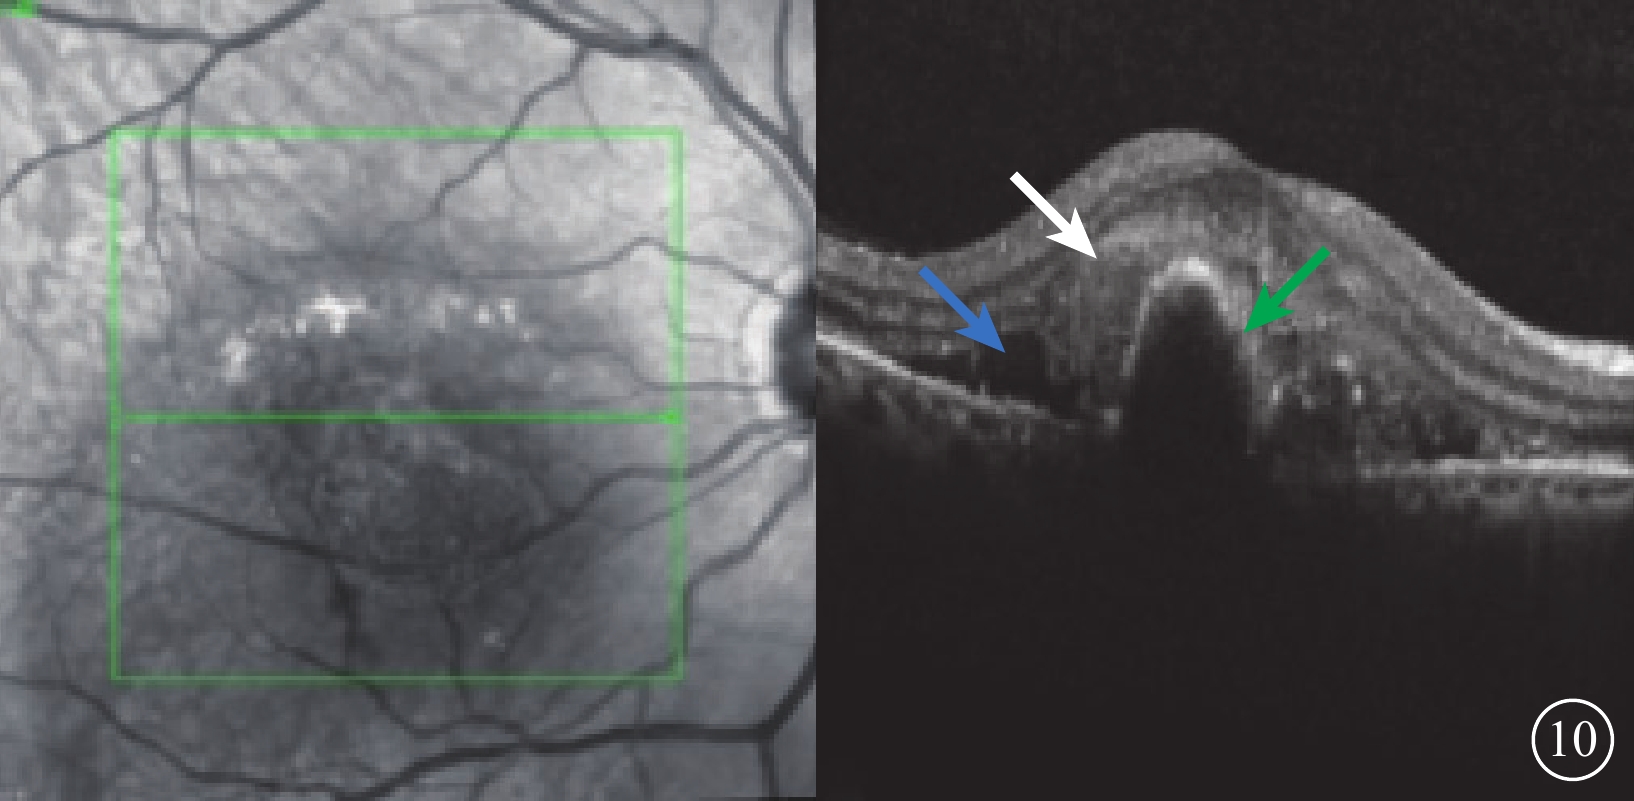

SHRM在OCT時代才被觀察到。它是指除了紅細胞之外的物質滲出到視網膜內或視網膜下,OCT表現為一些區域無特征性的蓄積物合并相對一致的增強反射(圖10)。這些物質多由血清、纖維蛋白和炎性細胞組成。不同于卵黃樣物質,SHRM在眼底自身熒光(FAF)檢查上并不顯示為強熒光。SHRM可以吸收,但纖維化常常出現[28-29]。當出現SHRM時,患者視力預后往往較差[27]。2型MNV的滲出會直接進入視網膜下腔,其存在SHRM的線索包括FFA的經典表現、外界膜破壞和視網膜內液體。SHRM的再出現是新生血管復發的標志[30]。

圖10

視網膜下液、SHRM及PED患眼OCT像。左圖為掃描方向和部位,右圖為檢查結果。視網膜下液(藍箭)、視網膜下反射均勻增強(白箭)及RPE隆起(綠箭)。SHRM:視網膜下強反射物質;RPE:視網膜色素上皮;PED:RPE隆起;OCT:光相干斷層掃描